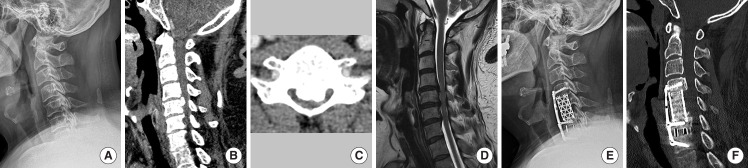

Methods: Patients with cervical myelopathy due to multilevel OPLL who underwent decompression surgery (anterior or posterior) from 2013 to 2022, with 2-year minimum follow-up, were enrolled. Radiological evaluations included K-line, COR, OPLL type/level, and cervical parameters (C2 slope [C2S], T1 slope [T1S], K-line tilt). Clinical outcomes included Japanese Orthopaedic Association (JOA) score and neck-pain visual analogue scale. Patients were categorized by K-line status (+/-) and COR (<50% or ≥50%).

Results: Among 575 patients, JOA recovery was significantly better in the K-line (+) and in low COR (<50%). In high COR (≥50%), K-line (-) was associated with poorer recovery. In low COR, outcomes were similar regardless of K-line. Anterior decompression with fusion (ADF) yielded the best outcomes. Laminoplasty (LP) was optimal for COR ≥50% and/or K-line (+), while laminectomy with fusion (LF) was better for COR ≥50% and K-line (-). In high COR, K-line was influenced by cervical alignment, C2S, and T1S, while in low COR, it was mainly affected by COR percentage.

Conclusion: Combining K-line and COR is essential for surgical planning in multilevel OPLL. When COR is high, K-line plays a significant role in predicting neurological recovery. ADF led to superior recovery, whereas for patients with K-line (-) and high COR, LF offered better results than LP. Cervical parameters at high COR influence the K-line more.